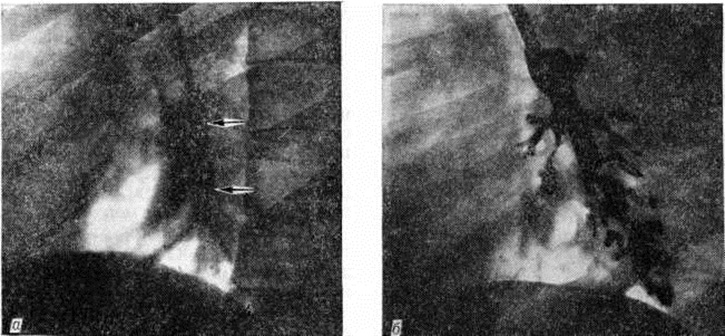

При определении Пневмосклероз наиболее характерны рентгенологические изменения, по которым можно судить об этом симптоме. Рентгено л. картина Пневмосклероз полиморфна, поскольку может отражать многообразные проявления склероза и сопутствующих ему хронический бронхита, бронхиолита, бронхоэктазов, эмфиземы, нарушений бронхиальной проходимости, интерстициальной и альвеолярной инфильтрации и гемостаза. Изменения при Пневмосклероз, связанные с поражением крупных, средних и мелких бронхов, улавливаются и на обычных рентгенограммах высокого качества, но особенно хорошо на электро-рентгенограммах (смотри полный свод знаний: Электрорентгенография) и томограммах (смотри полный свод знаний: Томография). Они состоят в усилении и деформации линейных элементов лёгочного рисунка по ходу бронхиальных разветвлений за счёт уплотнения стенок бронхов, инфильтрации и склероза перибронхиальной ткани и клетчатки корня лёгкого (рис 6.). На периферии лёгкого хорошо выделяются многочисленные линейные тени с неровными очертаниями, идущие в необычном направлении, часто создающие характерные многоугольные фигуры. В средней зоне лёгочного поля дифференцируются укрупнённые полосковидные тени с неправильными контурами, обусловленные появлением перибронхиальных уплотнений («муфт») вокруг просветов бронхов (рисунок 7). Признаки эмфиземы являются почти обязательными «знаками» Пневмосклероз такого типа. Так, феномен «сотового лёгкого», возникающий вследствие склероза стенок и расширения бронхиол в зоне поражения, на рентгенограммах имеет вид более светлых участков в форме розеток, обрамлённых дугообразными линиями уплотнённых междольковых перегородок. Эти просветления отличаются множественностью, типичной формой, тонкостью и чёткостью стенок, изменчивостью на снимках в разных проекциях. При поражении более крупных бронхов могут наблюдаться вздутия субсегментов или даже целых сегментов. Рубцовые изменения в лёгочной ткани в зависимости от их происхождения дают неодинаковую рентгенологическое картину. Для поражений, обусловленных интерстициальным хронический воспалительным процессом при лимфангиитах, саркоидозе, пневмоконнозах, типичен сетчатый лимфогенный Пневмосклероз Отёк и последующий склероз перилобулярной лимфатических, сети на снимках проявляется сетчатым рисунком. Межрёберные промежутки густо заполнены пересекающими друг друга тенями, имеющими неровные контуры и неравномерную ширину. Обилие сосудов, идущих ортоградно, обусловливает мелкую пятнистость. Наряду с сетчатым лимфогенным Пневмосклероз, особенно в поздних стадиях болезни, развивается очаговый или ограниченный сегментарный склероз. Если пусковым механизмом поражения являлся хронический бронхит, то преобладают небольших размеров округлые или продолговатые очаги рубцовой ткани, образовавшиеся на почве дольковых и пластинчатых ателектазов, а также пневмонических фокусов. Если Пневмосклероз явился результатом не разрешившегося инфильтрата или нерасправившегося ателектаза в пределах субсегмента или сегмента, то на снимках определяются более крупные участки затемнения, соответствующие полям карнификации и фиброателектазам. На томограммах в зоне поражения, которая, как правило, уменьшена в объёме и пронизана грубыми тяжами, видны просветы деформированных бронхов с бронхоэктатическими расширениями в дистальных отделах. Плеврогенный склероз развивается, как правило, в кортикальных отделах лёгкого. Вариабельность формы и конфигурации патологический тени во многом зависит от степени развития соединительной ткани, выраженности плевральных сращений, компенсаторного вздутия соседних участков лёгкого. Обнаружение на обзорных рентгенограммах и томограммах описанных изменений служит основанием для выполнения бронхологического исследования. Бронхография (смотри полный свод знаний) позволяет обнаружить сближение, деформацию и неровность контуров бронхов, а также различного типа бронхоэктазы (рисунок 8). Нарушение сократительной способности бронхов (бронхоспазм, бронходилатация, дискинезия) сочетается с изменением скорости и равномерности заполнения их контрастным веществом; периферические бронхи при этом не контрастируются. На ангиопульмонограммах (смотри полный свод знаний: Ангиопульмонография) в поражённой части лёгкого обнаруживаются замедление кровообращения, деформация и обеднение сосудистой сети, а в отдельных случаях полное прекращение кровотока. При бронхиальной артериографии (смотри полный свод знаний) выявляются изменения архитектоники, формы и протяжённости сосудов, функционирующие бронхиально-лёгочные, артерио-артериальные и артериовенозные анастомозы. Рентгенологические изменения при локальных формах Пневмосклероз в первую очередь необходимо дифференцировать с рентгенологическое картиной при центральном раке лёгкого (смотри полный свод знаний: Лёгкие). В пользу Пневмосклероз свидетельствуют неравномерность и полиморфизм инфильтративных и фиброзных изменений, наличие деформированных, но проходимых крупных и средних бронхов, смещённых вследствие сморщивания поражённой части лёгкого. В трудных для диагностики случаях решающие сведения могут быть получены с помощью бронхоскопии и эндобронхиальной биопсии (смотри полный свод знаний: Бронхоскопия). При распространённом Пневмосклероз дифференциальную диагностику проводят главным образом с системными заболеваниями, для которых характерно преимущественное поражение сосудов (васкулиты), а также с раковым лимфангиитом. При наличии хронический васкулита и периваскулита склероз стенок кровеносных сосудов, организация множественных мелких лёгочных эмболов ведут к лёгочной гипертензии и лёгочному сердцу, для которых характерно сочетание усиления сосудистого рисунка, мелкой сетчатостью за счёт расширения мелких сосудов, увеличения правого желудочка и расширения лёгочного ствола. При ряде заболеваний — склеродермии (смотри полный свод знаний), бериллиозе (смотри полный свод знаний: Бериллий), саркоидозе (смотри полный свод знаний) и другие— Пневмосклероз развивается в результате поражения преимущественно межальвеолярных перегородок. Фиброзные структуры образуют беспорядочную мелкую сетчатость и множественные мелкие кистоподобные кольцевидные тени (при склеродермии). Деформация лёгочного рисунка в результате венозного застоя и гемосидероза лёгких происходит главным образом за счёт патологии междольковой и внутридольковой соединительной ткани (нежная мелкая сетчатость). При проведении дифференциальной диагностики наряду с анализом рентгенологическое картины необходимо учитывать данные анамнеза, клинические, картину и лабораторный данные. Так, например, периацинозный и более грубый фиброз застойного происхождения (кардиогенный Пневмосклероз) распознаются на основании наличия в анамнезе ревматизма, клинико-рентгенологическое картины порока сердца, застойных корней лёгких, признаков застойного полнокровия в малом круге кровообращения. Для диагностики пневмокониоза большое значение имеет длительный профессиональный контакт больного с пылью, а для распознавания саркоидоза, помимо данных о динамике процесса, сочетание интерстициального фиброза и гиперплазии бронхолёгочных (корневых) лимфатических, узлов. Экзогенный Пневмосклероз при фиброзирующих альвеолитах, так же, как и синдром Хаммена — Рича, характеризуется генерализованным сетчатым фиброзом с преобладанием поражений в нижних отделах лёгких при отсутствии выраженных изменений бронхов и перибронхиальной ткани. Наибольшее значение в диагностике могут иметь результаты гистологический и цитологический исследования материала, полученного при трансбронхиальной биопсии лёгкого (смотри полный свод знаний: Бронхоскопия, бронхофиброскопия) и трансторакальной пункции. Рентгенологические распознавание осложнений Пневмосклероз состоит главным образом в своевременном выявлении абсцедирования в зоне ограниченных рубцовых изменений, тонкостенных полостей на фоне грубой фиброзной сетки, в оценке характера нарушений топографических взаимоотношений органов в грудной полости (при цирротических процессах), распознавании признаков лёгочного сердца в случаях распространённого поражения. Диффузные формы Пневмосклероз, как правило, сопровождаются прекапиллярной гипертензией малого круга кровообращения (смотри полный свод знаний) и легочным сердцем (смотри полный свод знаний), которые в значительной степени обусловлены причинами, вызвавшими Пневмосклероз, поэтому прямой корреляции между степенью выраженности, распространённости Пневмосклероз и высотой давления в системе лёгочного ствола не наблюдается. Локальные цирротические формы Пневмосклероз могут вызвать резкую деформацию грудной клетки, частичную атрофию грудных мышц, сморщивание меж рёберных промежутков, смещение трахеи, крупных сосудов и сердца в сторону поражения. Цирротическая деформация корня лёгкого с компрессионным стенозом отдельных сосудов в области ворот лёгкого способствует развитию аневризм (смотри полный свод знаний: Аневризма) в ветвях как бронхиальных, так и лёгочных артерий, которые могут служить источником тяжёлых кровотечений. Пневмосклероз способствует развитию рака лёгкого, который, как показали статистические исследования В. И. Брауде (1971), чаще развивается при неспецифических формах Пневмосклероз Среди больных туберкулёзом рак чаще встречается на фоне затухшего рубцового процесса. Лица с Пневмосклероз различной локализации и распространённости обладают также высоким риском возникновения туберкулёза. По данным М. В. Шилова и Е. В. Полетило (1976), такие больные составляют 22,5% всех впервые взятых на учёт в противотуберкулёзных учреждениях. Имеются данные о возможной обратимости Пневмосклероз Впервые о декарнификации сообщил М. К. Даль (1956), наблюдавший лизис коллагеновых волокон макрофагами. А. Б. Шехтер (1978) описал ультраструктурные признаки лизиса коллагеновых фибрилл особыми клетками — фиброкластами. Реже обнаруживается фиброклазия в миофибробластах. Катаболизм коллагенообразования и рассасывания определяется рядом гуморальных факторов. Однако, возникнув, Пневмосклероз способствует прогрессированию воспалительных процессов, нарушению трофики и лимфообращения, поэтому профилактика его должна осуществляться в возможно ранние сроки. Профилактика заключается в предупреждении, а также в своевременном и рациональном лечении лёгочных инфекций, в борьбе с интоксикациями, прежде всего с загрязнением окружающей среды и курением, особенно в юношеском возрасте. Профилактика Пневмосклероз должна проводиться с детства, так как часто повторяющиеся катары верхних дыхательных путей, грипп, а также корь, коклюш могут привести к хронический бронхитам — основной причине Пневмосклероз. Особое внимание должно быть направлено на тщательное долечивание пневмоний, бронхитов, устранение аллергизирующих факторов, следует с осторожностью назначать лекарственные средства, учитывая их индивидуальную непереносимость, и своевременно их отменять в случае развития аллергии. Необходима санация очагов инфекции, в первую очередь в носоглотке, полости рта. При развитии хронический бронхита рекомендуется смена профессии, если она связана с вдыханием пыли. Развитие Пневмосклероз тормозят иммунодепрессанты, антигистаминные средства; резорбции коллагеновых волокон в рубцах способствуют препараты гиалуронидазы.